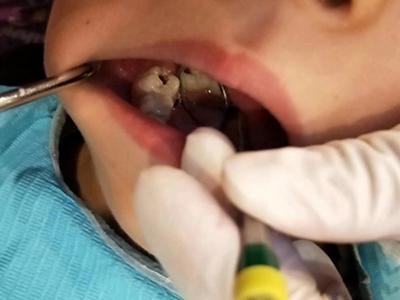

年轻恒牙龋一般可进行充填治疗,对于早期的年轻恒磨牙,提倡采用微创的预防性树脂充填术、改良的预防性树脂充填术;深龋必要时考虑二次去腐修复。日常注意饮食,重视口腔卫生,考虑局部使用氟化物防龋,如含氟牙膏、含氟漱口水等,进行预防。对于年轻恒磨牙,可早期进行窝沟封闭,定期进行口腔检查。